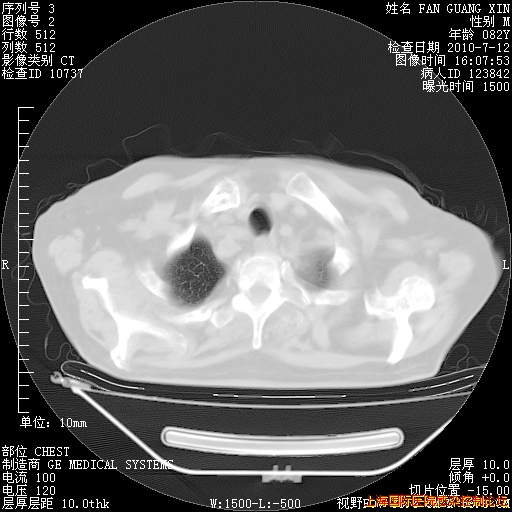

补发6月12日肺部CT肺窗

6月12日肺窗